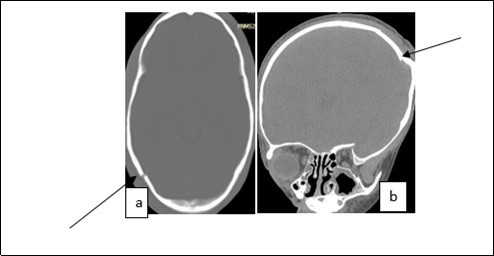

From the point of view of care, two (n=2) (10.52%) children received medical treatment compared to 17 (89.48%) children who received medical-surgical treatment. Neurosurgical treatment consisted of evacuation of the extra dural hematoma. This involved making a skin incision, trepanation (Figure 3 a), a preserved cranial bone flap, evacuation of the extra-dural haematoma (Figure 3 b), haemostasis either of the bone using bone wax or venous or arterial haemostasis by bipolar coagulation as appropriate, suspension of the dura mater (Figure 3 c), replacement of the bone flap (Figure 3 d) and finally suturing of the scalp in two planes. Figure 1, Figure 2, Figure 3.

Figure 2.Image of a brain CT scan without contrast agent injection in a bone window, axial section showing a right parieto-occipital fracture (a), coronal section showing a left parietal skull depressed fracture (b)